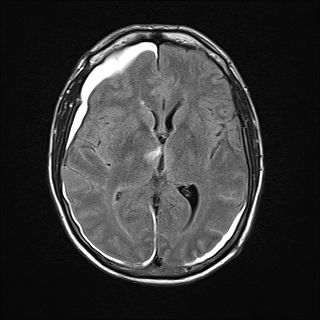

The findings in our patient of vertical gaze palsy in both up and down gaze, bilateral abduction deficits (likely pseudoabducens palsy) localized to a lesion in the mesodiencephalic junction in the territory supplied by the posterior thalamo-subthalamic paramedian artery, a branch off the tip of the basilar artery. MRI confirmed a subacute infarction in this region (See Figure 3A, 3B, 3C, 3D). The infarction may have been caused by compression or disruption by coiling of the posterior thalamo-subthalamic branch of the paramedian artery.

Figure 3

Figure 3C. MRI Flair image showing hyperintensity in the Rostral midbrain Figure 3D. MRI Flair image showing hyperintensity in the right thalamus. Also note hyperintense signal from subarachnoid hemorrhage